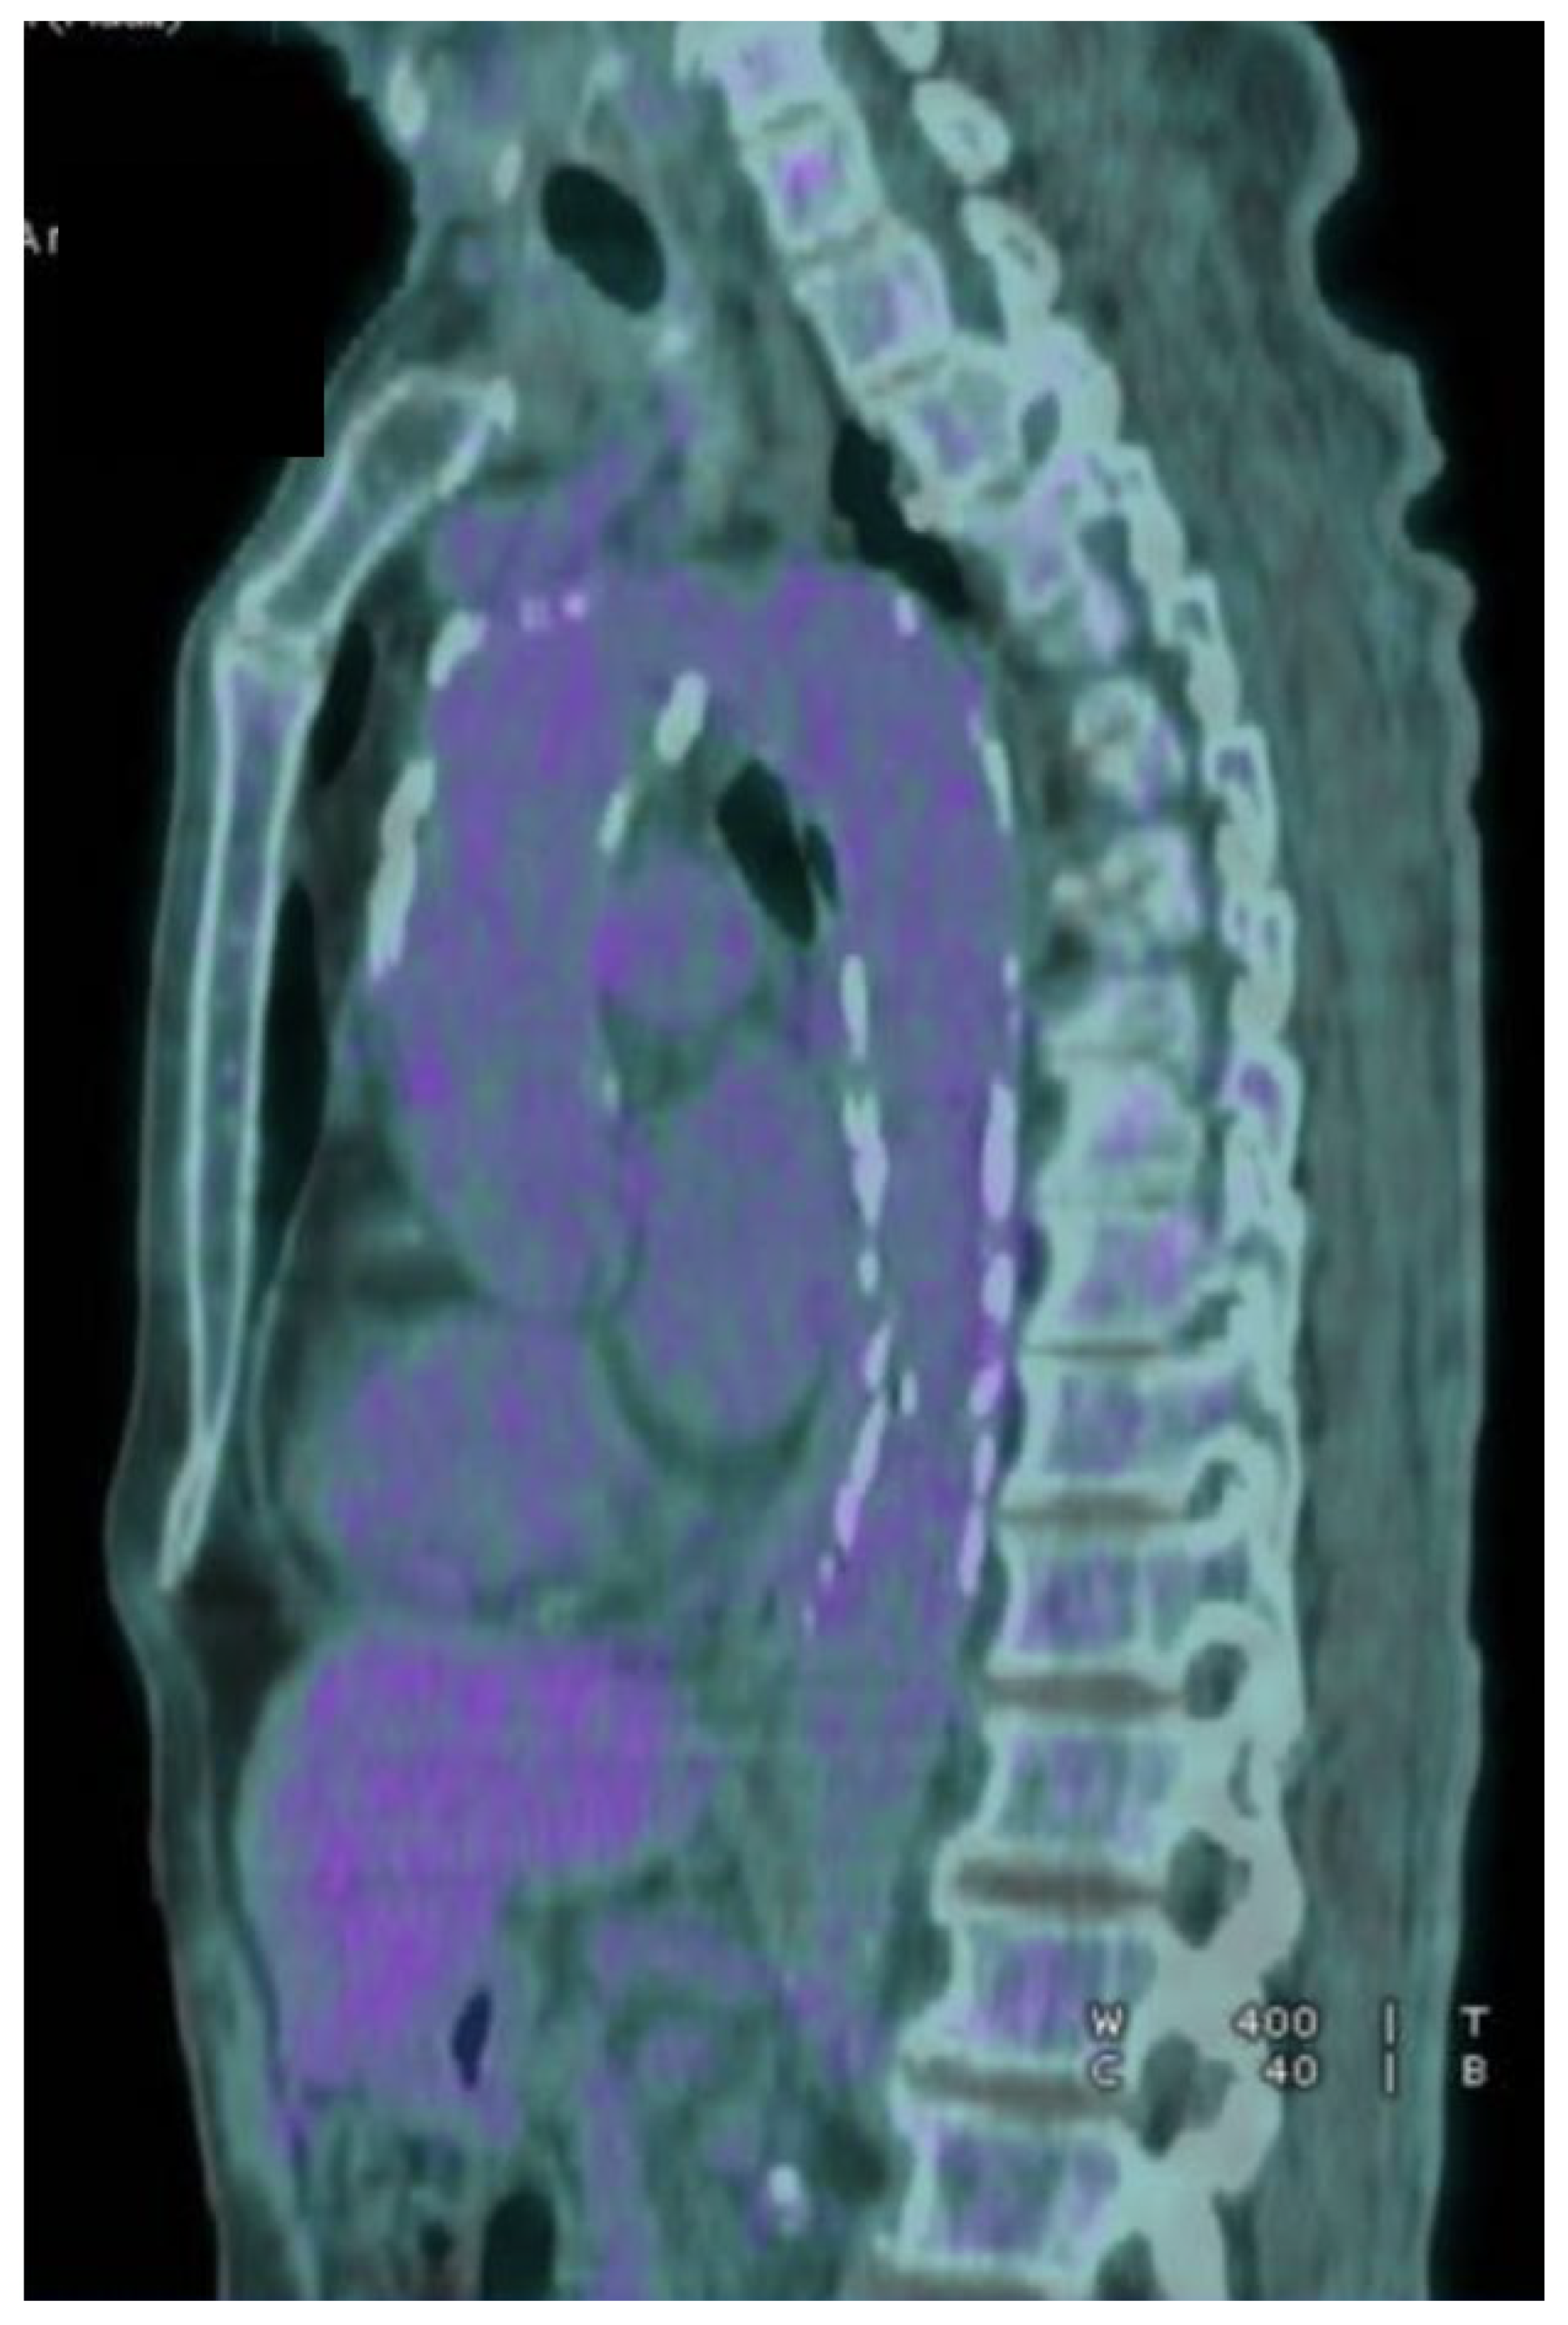

2.1. Case 1

2.2. Case 2